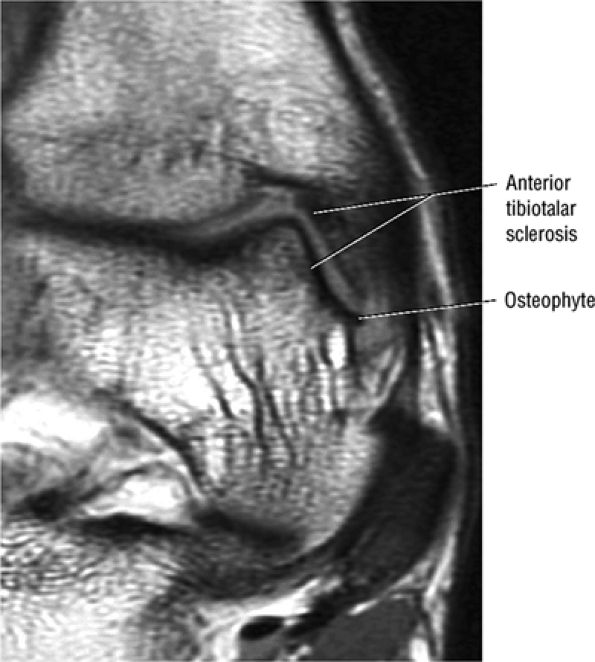

Anterior osseous impingement of the ankle with spurring of the anterior aspect of the tibiotalar joint and bone marrow edema demonstrated in the anterior distal tibia